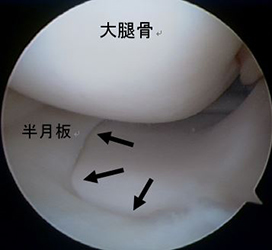

半月板損傷

半月は、膝関節の大腿骨と脛骨の間にあるC型をした軟骨様の板で内側・外側にそれぞれがあり、クッションとスタビライザーの役割をはたしています。半月板損傷は、スポーツ外傷や加齢性の変化などにより、幅広い年齢層に生じます。症状は、引っかかり感や関節が曲がらない・伸びないなどの関節可動域制限、しゃがんだ際などの痛みであり、痛みがひどい場合には、夜間寝返りで目が覚めることもあります。半月板は損傷すると治りにくい組織です。保存的治療で症状改善が得られない場合、関節鏡視下の半月板部分切除術や縫合術をお勧めします。

関節鏡視下半月板部分切除術・縫合術

本手術は内視鏡を用いて行うため、少数の小さい傷で低侵襲に行う事ができます。可及的に縫合し半月板の温存を試みますが、損傷形態によっては部分切除を選択します。リハビリは、術翌日より積極的に行い、スポーツ復帰や社会復帰に向け準備致します。

前方に逸脱した外側半月板を整復し縫合した。